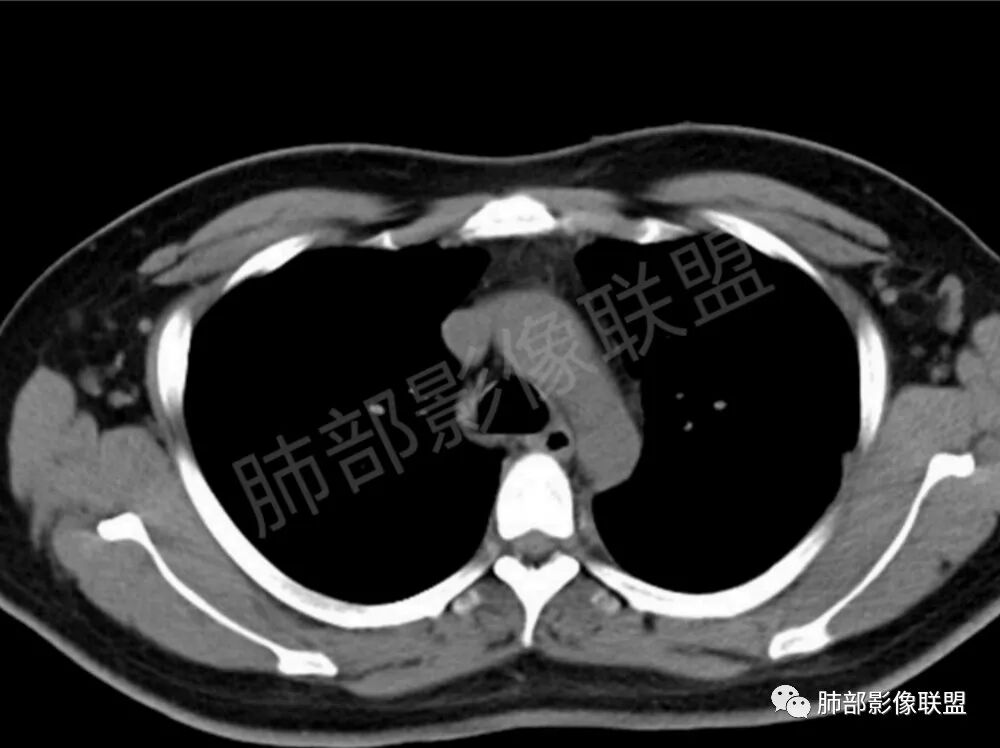

两肺多发结节性,大部分位于胸膜下,部分结节周围可见晕征。局部结节内可见扩张的支气管,纵隔淋巴结大,脾大,22岁男,HIV阳性,常规先考虑隐球菌。鉴别淋巴瘤,结核,马儿。

男,22,半年前咳嗽伴少痰,查HIV阳性,痰查TB阳性,既往有肺部斑片影伴空洞、纵隔淋巴结肿大、脾大。SCC、CA50、CA199、FER增高,此次胸部CT:两肺多发结节影,部分沿血管束分布,部分贴胸膜下,大小不一,密度不一,部分较散、边缘模糊,部分较实、圆钝、周围模糊晕,部分结节有支气管进入穿行自然,部分结节有血管分支自如通过。考虑HI∨相关淋巴增殖类病变,淋巴瘤?LYG?鉴别PC、TB。

青年男性,半年前咳嗽,HIV阳性,结核DNA阳性,肿标糖类抗原和铁蛋白增高。外院影像有纵隔淋巴结增大伴脾大,肺部病灶空洞。现在影像:肺内多发沿支气管分布(有支气管充气征,长轴沿支气管分布)及胸膜下分布(平行于胸膜)的大小不等结节,个别伴有空洞,双侧腋窝淋巴结肿大。纵隔图片不够,是否还有淋巴结肿大未知,脾脏未显示。

1、HIV相关淋巴瘤,有HIV阳性,有纵隔及腋窝淋巴结肿大,肺内病灶沿支气管分布(中轴淋巴间质)及胸膜下分布(周围淋巴间质),有脾大,这个是必须要考虑的。但是原来的影像是肺斑片影伴空洞,又有疑问,需要穿刺明确。

影像学缺乏特征性,以支气管血管周围、胸膜下及双肺下叶周边多发结节影最多见,结节易坏死形成空洞,伴有游走性和多变性的特征,结节周围可有磨玻璃样晕征,有时也可见单发结节影、薄壁的囊状阴影或弥漫性浸润影。肺门、纵隔淋巴结肿大少见, 可见胸腔积液和气胸。